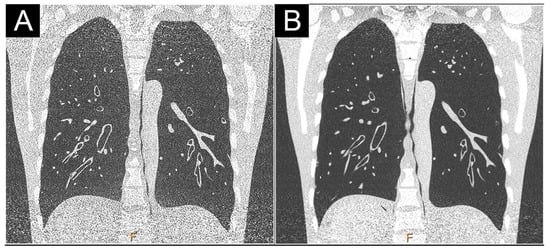

- Symons, R.; Pourmorteza, A.; Sandfort, V.; Ahlman, M.A.; Cropper, T.; Mallek, M.; Kappler, S.; Ulzheimer, S.; Mahesh, M.; Jones, E.C.; et al. Feasibility of Dose-reduced Chest CT with Photon-counting Detectors: Initial Results in Humans. Radiology 2017, 285, 980–989. [Google Scholar] [CrossRef] [PubMed] [Green Version]